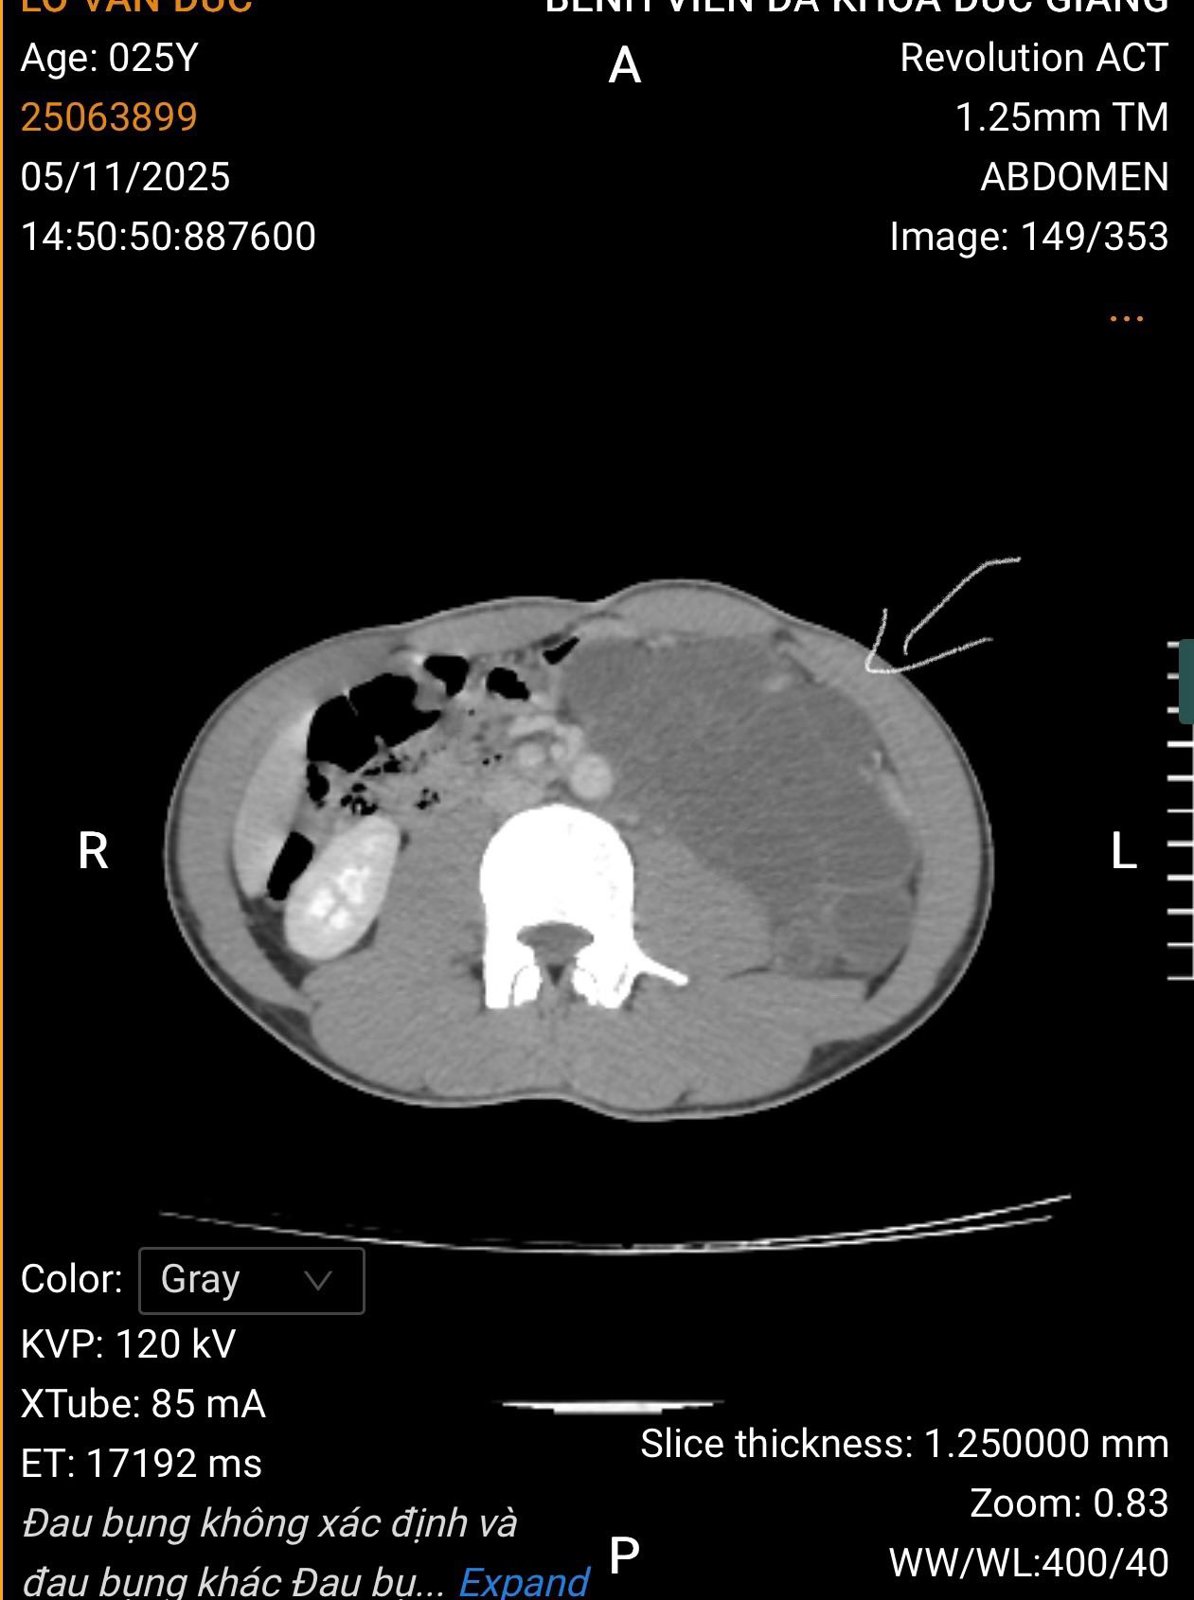

Các bác sĩ khoa Ngoại tổng hợp, Bệnh viện Đa khoa số 3 tỉnh Lào Cai vừa phẫu thuật thành công cho bệnh nhân L.V.Đ., 25 tuổi, quê Nậm Có – Lào Cai, mắc u Lymphangioma sau phúc mạc rất lớn biến chứng chèn ép tạng, một bệnh lý hiếm gặp và phức tạp.

Lymphangioma là một khối u lành tính hiếm gặp, phát triển từ hệ bạch huyết, thường xuất hiện ở trẻ em nhưng cũng có thể gặp ở người lớn. Khối u có thể xuất hiện ở nhiều vị trí, trong đó lymphangioma sau phúc mạc rất hiếm, thường tiềm ẩn nguy cơ chèn ép các tạng quan trọng.